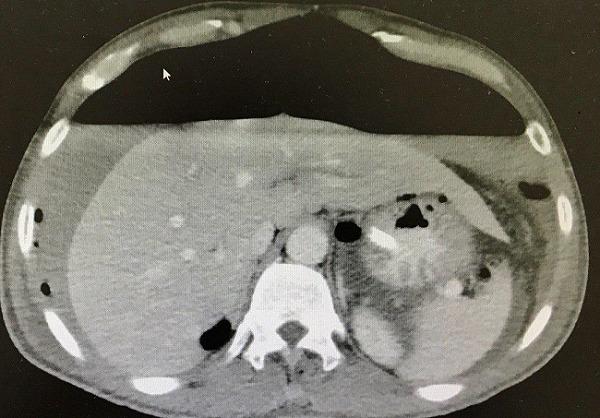

This case has interesting images of huge hydro pneumoperitoneum. It is a rare view in the medical practice and a good point to learn one of the complications of perforated duodenal ulcer and failure of omental patch operation. We reported a case of acute abdominal pain with hydro pneumoperitoneum that appeared as an air fluid line in X-ray. The patient had an omental patch surgery. Two days after the operation he got severe abdominal pain. The X-ray images showed significant huge hydro pneumoperitoneum. He underwent urgent surgical intervention for exploration that detected a large amount of gases, a biliary free fluid and a leak from duodenal ulcer. Omental buttressing was then performed.

该病例有巨大气腹积气的有趣影像。这在医学实践中是一种罕见的情况,也是了解十二指肠溃疡穿孔和网膜修补手术失败的并发症之一的好机会。我们报告了一例急性腹痛伴气腹积气的病例,X线显示为气液平面。该患者接受了网膜修补手术。术后两天,他出现剧烈腹痛。X线影像显示有明显的巨大气腹积气。他接受了紧急手术探查,发现大量气体、无胆汁的液体以及十二指肠溃疡渗漏。随后进行了网膜支撑术。